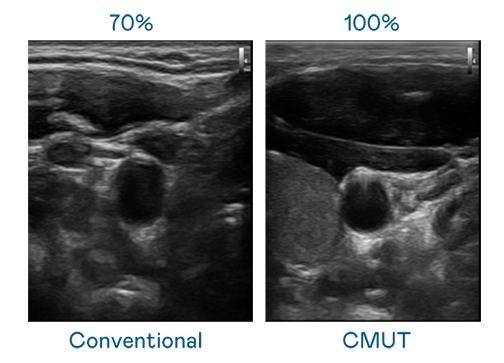

CMUT 技術是一種用電容式微機電元件來產生超音波訊號的技術。與傳統 PZT 壓電式技術相比,CMUT 頻寬增加 30%,更寬頻的超音波訊號讓影像解析度大幅提升,是實現高影像品質醫療超音波掃描、促進精準醫療發展的關鍵技術。

超音波影像的解析度高低,首先取決於探頭能發出的訊號頻寬。AG百家乐 CMUT 可提供高清晰的超音波訊號,提供高頻寬、高靈敏度、影像紋理細節更高的超音波影像,協助醫護人員縮短影像判讀時間及利用精準的醫療影像進行診斷。